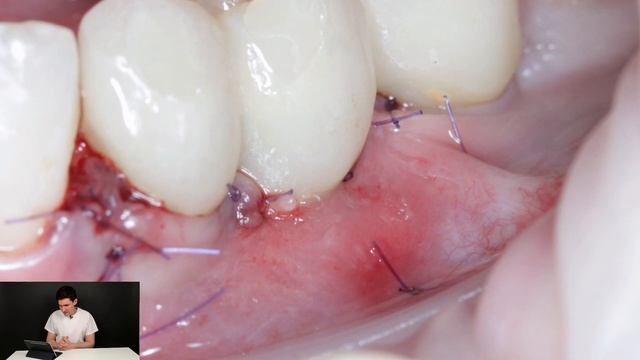

Мягкотканная пластика. Протокол увеличения объема мягких тканий вокруг имплантата.